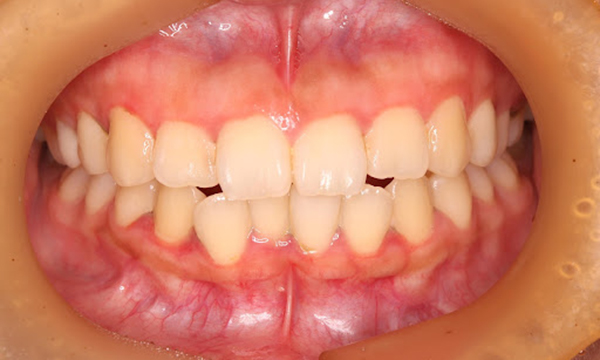

症例4

before

症例

after

基本情報

年齢・性別 26歳・男性

主訴 主訴:左下親知らず痛い

治療部位:左下8番

治療内容 ・左下8番埋伏抜歯

〈歯周病治療〉

①検査、資料取り(歯周ポケット検査、レントゲン14枚法、口腔内写真)、染めだし、歯磨き指導

②歯肉縁上の歯石除去、歯磨き指導、確認

③歯肉縁下の歯石除去(SRP)

④再評価

⑤メインテナンス

(2024年8月現在)

治療期間 約1ヶ月

治療費 合計:19,950円

〈内訳〉(全て保険診療3割負担)

①初診検査、左下8番埋伏抜歯:10,620円

②染めだし・歯磨き指導:1,110円

③歯磨き指導、確認・縁上歯石除去:2,830円

④縁下歯石除去(SRP)×2回:1,680円(×2回)

⑤再評価(歯周精密検査)・歯磨き指導:2,030円

治療方針 左下の親知らずが痛いとのことでご来院された患者さまです。

親知らず周囲は汚れが落としきれておらず、歯ぐきが炎症を起こしている状態でした。

当日抜歯を希望されていたので、麻酔を効かせてから三次元的なレントゲン写真(CT)撮影し、抜歯を行いました。

その後、全顎的に歯石付着、歯ぐきの炎症が見られたので歯周病治療をその他の治療と並行して行っていきました。

担当者所見 初診時は歯ブラシの交換時期を把握していなかった患者さまが歯ブラシを新しくしてから約1ヶ月後自分から歯ブラシを変えたことを教えてくださいました。

歯周病治療を進めていくうちに、患者さまの口腔内への意識が高まっていて治療が良い方向に進んでいきました。

歯周基本治療とセルフケアで歯ぐきの炎症や出血は初診時より大分改善されましたが、出血率を0%まで減らしていけるように今後は定期的な検診で歯ブラシの当て方や経過を患者さまと一緒に確認していこうと思います。